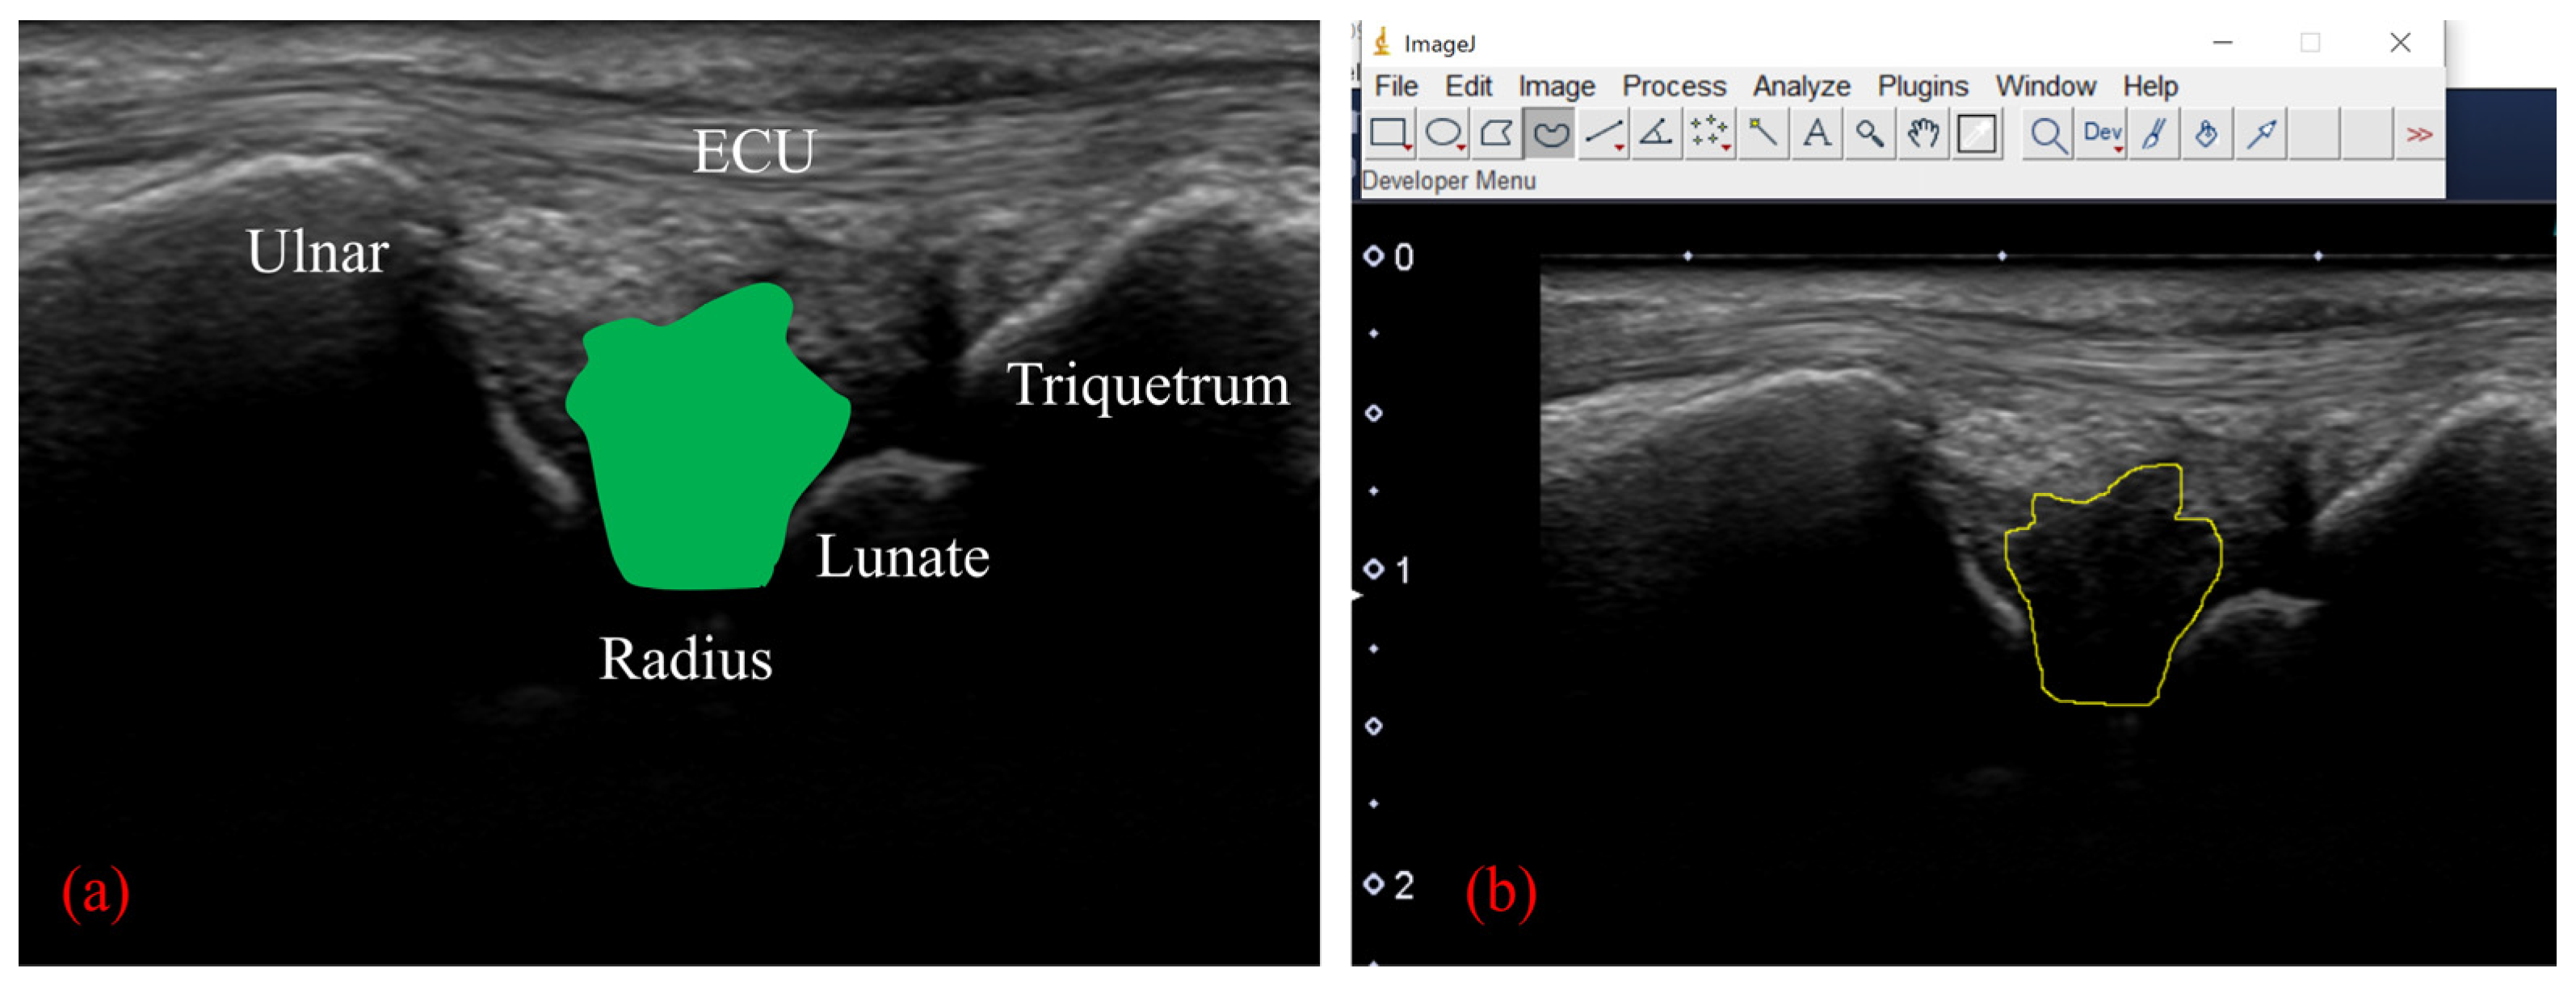

On US imaging, the TFCC was visualized from its dorsal side with the forearm in pronation, using a 15M linear probe (Canon Aplio 300, TUS-A300, Canon Medical Systems, Tochigi, Japan). The gain, dynamic range, and frame rate were kept constant throughout all measurements and were not changed between participants. Following the procedure reported by Wu et al. [5], the US transducer was positioned between the ulnar styloid process and the triquetrum, parallel to the ECU tendon, with a 30-degree ulnar tilt from the vertical line (Figure 3). In this view, a hyperechoic ECU tendon could be observed as the most superficial structure. The ulnar collateral ligament could then be seen as a hyperechoic fibrillary structure beneath the ECU tendon. The lunate and triquetrum could be seen on the distal side of the view and the ulnar styloid process on the proximal side; each was covered by an anechoic layer of cartilage. The articular disc appeared as a hypoechoic structure between the ulna and lunate. The lunotriquetral ligament, which links the lunate and triquetrum, also appeared as a hypoechoic structure on the surface of two carpal bones. Between the triquetrum and the articular disc, the hammock-shaped meniscus homolog could be seen as a mixture of hyperechoic and hypoechoic structures (Figure 3).

Figure 3.

(a) Ultrasonography (US) transducer was positioned between the ulnar styloid process and the triquetrum, parallel to the extensor carpi ulnaris (ECU) tendon, with a 30 degree ulnar tilt from the vertical line. With this view, the wrist joint was moved from 15° of radial flexion to 25° of ulnar flexion. (b) US imaging of the TFCC by using the long-axis approach. (c) With this view, we can observe the ECU tendon, ulnar collateral ligament (light blue shade), meniscus homologue (orange shade), radioulnar ligament (yellow shade), articular disc (green shade), and lunotriquetral ligament (light purple shade).

To perform motion analysis, TFCC visualization was performed with the forearm in pronation. Under these views, the wrist was actively moved from 15 degrees of radial deviation to 25 degrees of ulnar deviation at a 60-rounds-per-minute rhythm that was paced by a metronome (Figure 3). The same examination was performed twice per wrist. All US images were evaluated by two examiners (both senior orthopedic surgeons). As described previously, the articular disc was detected as a hypoechoic area [5]. Its area of measurement was defined by four lines as follows: proximal end of the articular disc, distal end of the articular disc, ulnar collateral ligament, and joint space between the lunate and triquetrum (Figure 4a). The area was calculated by using ImageJ software (USA National Institutes of Health [NIH], Bethesda, MA, USA), which is a public-domain Java-based image-processing software developed at the United States NIH [12]. Briefly, the areas of the defined articular disc were manually plotted and measured by using the Image J measurement tool (Figure 4b). Then, a comparison of the area of the articular disc between radial and ulnar deviation was performed. Furthermore, a correlation between patient height and the mean area of their articular disc was calculated. Measurements were performed by three orthopedic surgeons, using Image J. To confirm reproducibility, we calculated the intra-rater correlation coefficient and the inter-rater correlation coefficient by using these measurement results. Using the same images, the velocity magnitude of the articular disc displacement or ECU motion was analyzed by using PIV fluid measurement software (PIV lab. Version 2.36, add-in software from MATLAB (Mathworks, Natick, MA, USA)) [9]. Briefly, two regions of interest were set at the articular disc and ECU tendon (Figure 5). We edited all US movies into 30 static images per second. The pixel displacement between two sequential images was measured, and the velocity magnitude of the structure inside the region of interest was subsequently calculated. For the articular disc, the u-component, which comprises the longitudinal movement of the articular disc, was calculated. The v-component, representing the overall axial movement of the articular disc, was also calculated. Since the u- and v-components show positive and negative values depending on the direction of movement, the evaluation was added to the absolute values. PIV measurements were performed twice, with three examiners performing the measurements. The inter-rater and intra-rater correlation coefficients were evaluated.

Figure 4.

(a) We calculated the area of the articular disc up to the depth of the lunate cartilage (green area). (b) Calculation of the area using ImageJ software. The low-echo articular disc was manually plotted and measured with a measurement tool of Image J.